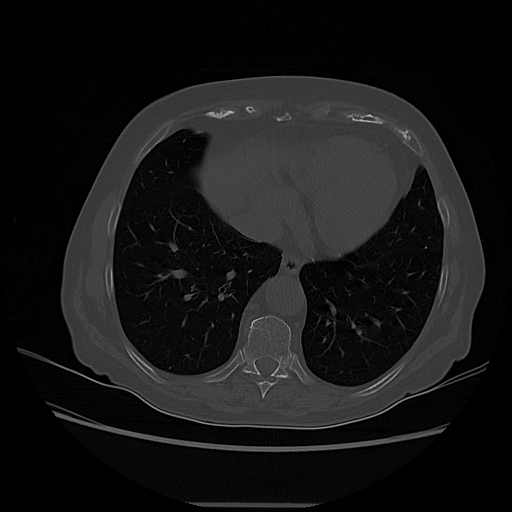

Original VENOUS CT scan

Lung window (WL -600, WW 1500 β†’ Low βˆ’1350, High +150)

Targeted Slice 70 - Lung Window Analysis (Generated vs Real Venous)

0.654

Lung SSIM

173.9

Lung RMSE

69.6

Lung MAE